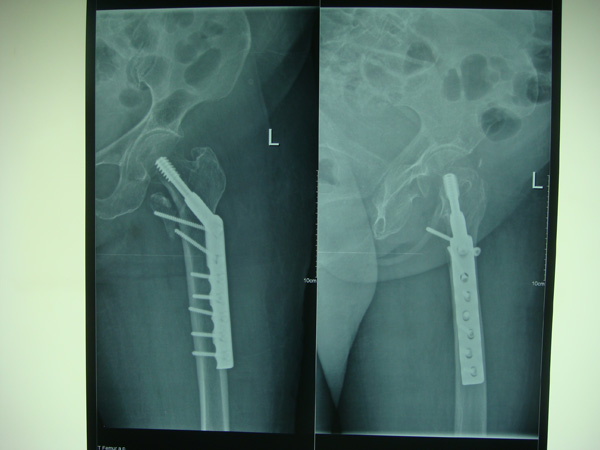

7月9日,莆田盛興醫(yī)院為一名89歲的女性髖部骨折患者順利實施了手術(shù)。